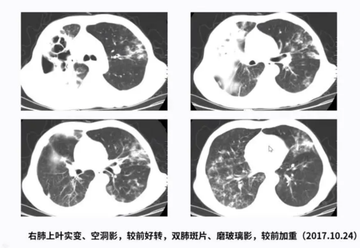

肺炎克雷伯菌肺炎是由肺炎克雷伯菌感染所致的细菌性肺炎肺炎克雷伯菌肺炎,占社区获得性肺炎的18%~64%,占医院内获得性肺炎的30%。克雷伯菌在自然界普遍存在。在人体免疫功能受损的情况下,肺炎克雷伯菌可侵入人体。肺炎克雷伯菌肺炎起病急,常有咳嗽、咳痰(砖红色胶冻样痰)、胸痛、呼吸困难、发热和寒战等症状。部分患者可有消化道症状,如恶心、呕吐、腹泻,少数有黄疸(皮肤、眼白发黄)。肺炎克雷伯菌肺炎的治疗包括抗感染治疗、通气和支持治疗、手术治疗。这些措施可以有效控制感染,改善预后。肺炎克雷伯菌肺炎可导致肺组织坏死,治疗后也可遗留局部纤维化、未闭合空洞和肺容积缩小,严重损害肺功能。还可并发脓胸支气管肺瘘形成、胸膜粘连、多重感染、心包炎关节炎脑膜炎等疾病。预后差,病死率较高,为20%~30%。